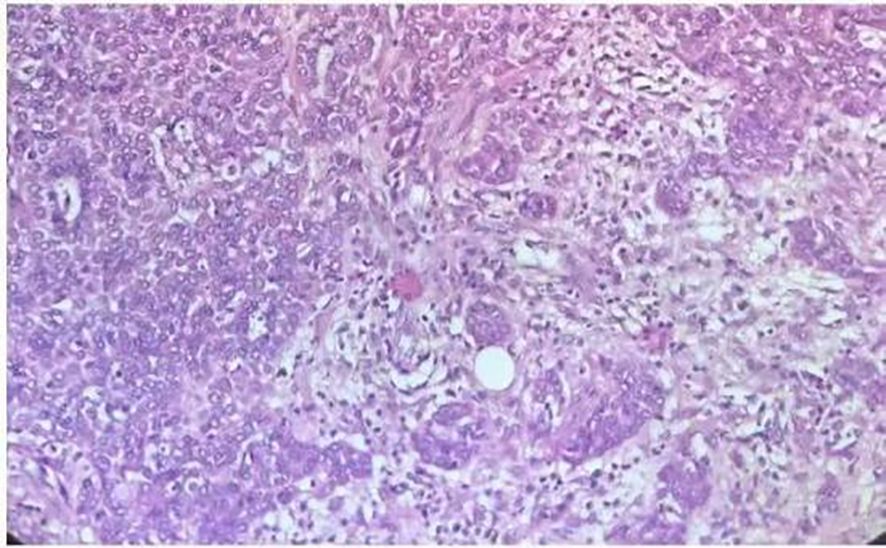

Postoperatively, 5 ml of 2% lidocaine was sprayed into the endotracheal tube to provide sufficient surface anesthesia and improve patient tolerance. The patient was transferred to the post-anesthesia care unit (PACU); he regained consciousness 10 minutes later and was transferred to the ward with the endotracheal tube after 1 hour of observation. Oxygen supplementation was continued via the tube at 2 L/min. Vital signs were as follows: SpO2 99%, blood pressure 152/78 mmHg, HR 82 beats/min, and body temperature 37.0°C. On postoperative day 1, the endotracheal tube was extubated. On postoperative day 2, the patient exhibited no hoarseness, sore throat, or speech impairment. Histopathological analysis confirmed a pleomorphic adenoma exhibiting invasive growth and focal malignant transformation consistent with myoepithelial carcinoma (Figure 3). Immunohistochemical staining revealed the following profile: AE1/AE3 (+), Vimentin (+/-), CK5/6 (+), P63 (+), GFTP (-/+), Calponin (+), S100 (focal +), Ki67 (positive cells accounting for 15% in high-expression areas), CD117 (+/-), CK7 (+). All clinically submitted margin specimens, including intratumoral marginal tissue, extratumoral marginal tissue, superior marginal tissue of the tumor, and inferior marginal tissue of the tumor, were negative for tumor involvement. The patient was successfully discharged on postoperative day 10. Telephone follow-up at 6 months post-surgery indicated stable clinical status. The timeline of the case report is shown in Table 1.

Figure 3. Hematoxylin and eosin-stained(×200)section showing features of pleomorphic adenoma with invasive growth characteristics.